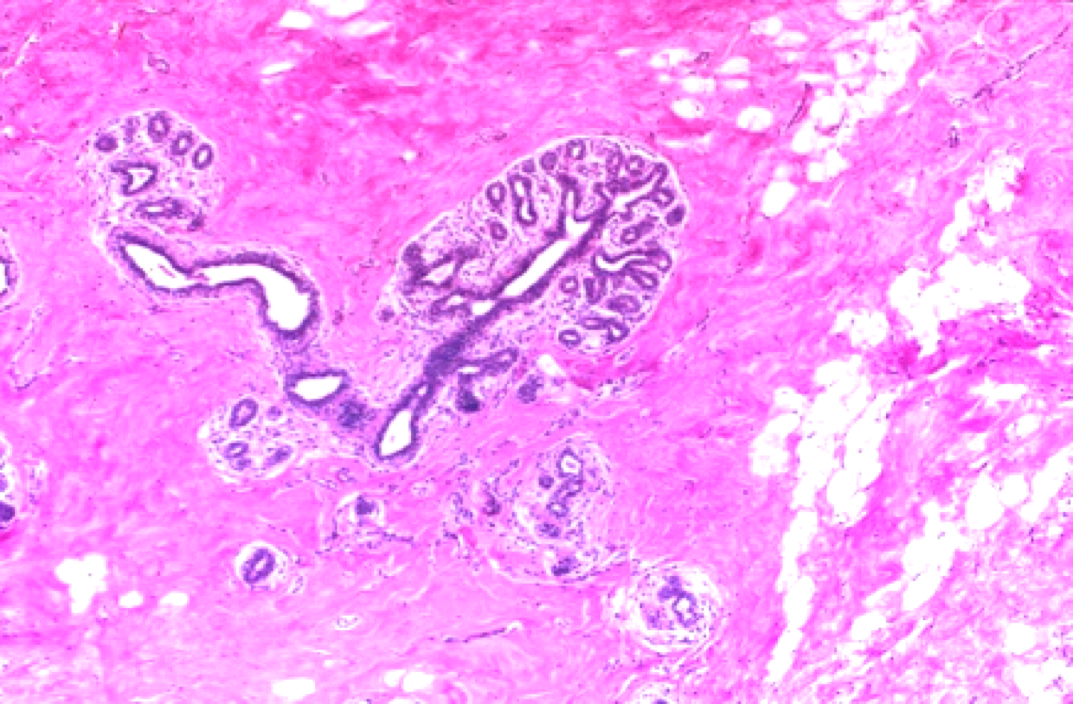

What is this an image of?

Normal breast: Ducts lined by double layer of epithelial cells and surrounded by layer of myoepithelial cells